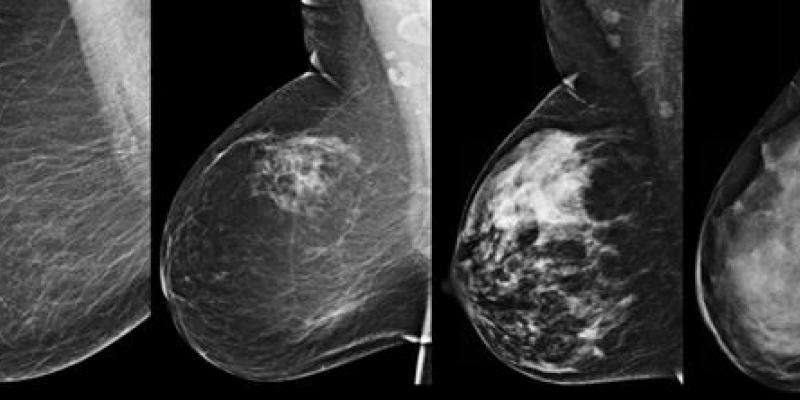

Mamografia